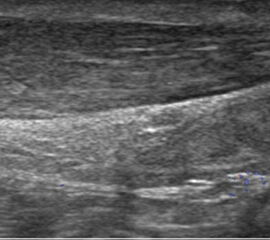

Die Sonographie zeigt im Falle einer Plantarfasziitis eine Verdickung der Plantarfaszie 24. Sie tritt etwas verzögert nach stattgehabter Überlastung und dem Schmerzbeginn auf und ist in ihrem Ausmaß ein guter Indikator für die Schwere der Erkrankung und die zu erwartende Behandlungsdauer. Die Rückbildung der Verdickung benötigt auch nach erreichter Schmerzfreiheit Wochen bis Monate.

Die sonographische Diagnostik eignet sich primär zur Erkennung schmerzhafter Prozesse im Verlauf der Achillessehne und kann bei Bedarf durch Röntgen bzw. MRT ergänzt werden. Besonders bei längeren Verläufen und kräftigen spindelförmigen Schwellungen (>9mm, Normwert <5mm) im Bereich der kritischen Zone sollte ein MRT zum Ausschluss von Nekrosezonen und Partialrupturen vor Therapiebeginn veranlasst werden. Die sonographisch leicht zu erfassende Veränderung der Sehnendicke im mittleren Sehnenanteil ist ein guter Indikator für die Schwere der Erkrankung und die Beurteilung des Behandlungsverlaufes. Die sichtbaren Veränderungen am distalen knöchernen Ansatz der Sehne sind diskreter.